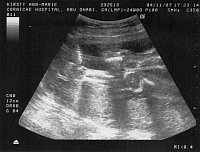

After

the trip we stopped a night in Hong Kong where I had my 19 week scan and

all seemed fine with a very active little baby in there - I also managed

to pick up the photo from my 12 week scan - so here it is - and what an

attractive blob it is too!!

Scan at 36 weeks - Basil

is lying sideways and you can see it's eyes and mouth and the fingers of

it's right hand which is on it's head, and left hand below it's face.

It's lying sideways in my tummy with it's head down getting ready to go